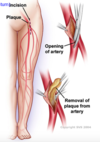

What is atherosclerosis?

Thickening of the artery wall as a result of the accumulation of calcium and fatty materials (cholesterol)

What does the thickening of the artery wall in atherosclerosis lead to?

Leads to reduced elasticity of the artery walls – allows less blood to travel through and increases blood pressure

What happens when plaque is deposited in the artery in atherosclerosis?

Plaque deposits can expand and cause blockage of the artery or lead to a thrombus formation, or can break away as an embolus and occlude smaller downstream branches